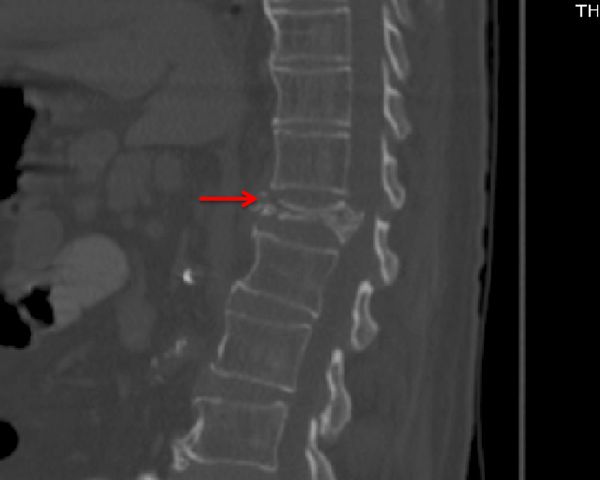

Спиральная компьютерная томография (СКТ). С помощью СКТ можно более точно оценить перелом: определить его уровень, количество повреждённых позвонков, выявить переломы дужек и др. Также СКТ позволяет увидеть сместившиеся костные отломки, которые не видны на рентгене.

![Перелом позвоночника на КТ [5] Перелом позвоночника на КТ [5]](/media/bolezny/perelom-pozvonochnika/perelom-pozvonochnika-na-kt-5_s.jpeg)

Перелом позвоночника на КТ [5]

Не всегда требуется выполнять все перечисленные исследования. Наиболее оптимальными методами являются СКТ и МРТ. Они позволяют установить правильный диагноз у 95–98 % больных. В отделениях реанимации рентгенография позвоночника у 80–90 % больных неинформативна, поэтому целесообразно сразу провести спиральную КТ всех отделов позвоночника, а при подозрении на сочетанную травму — СКТ всего тела.